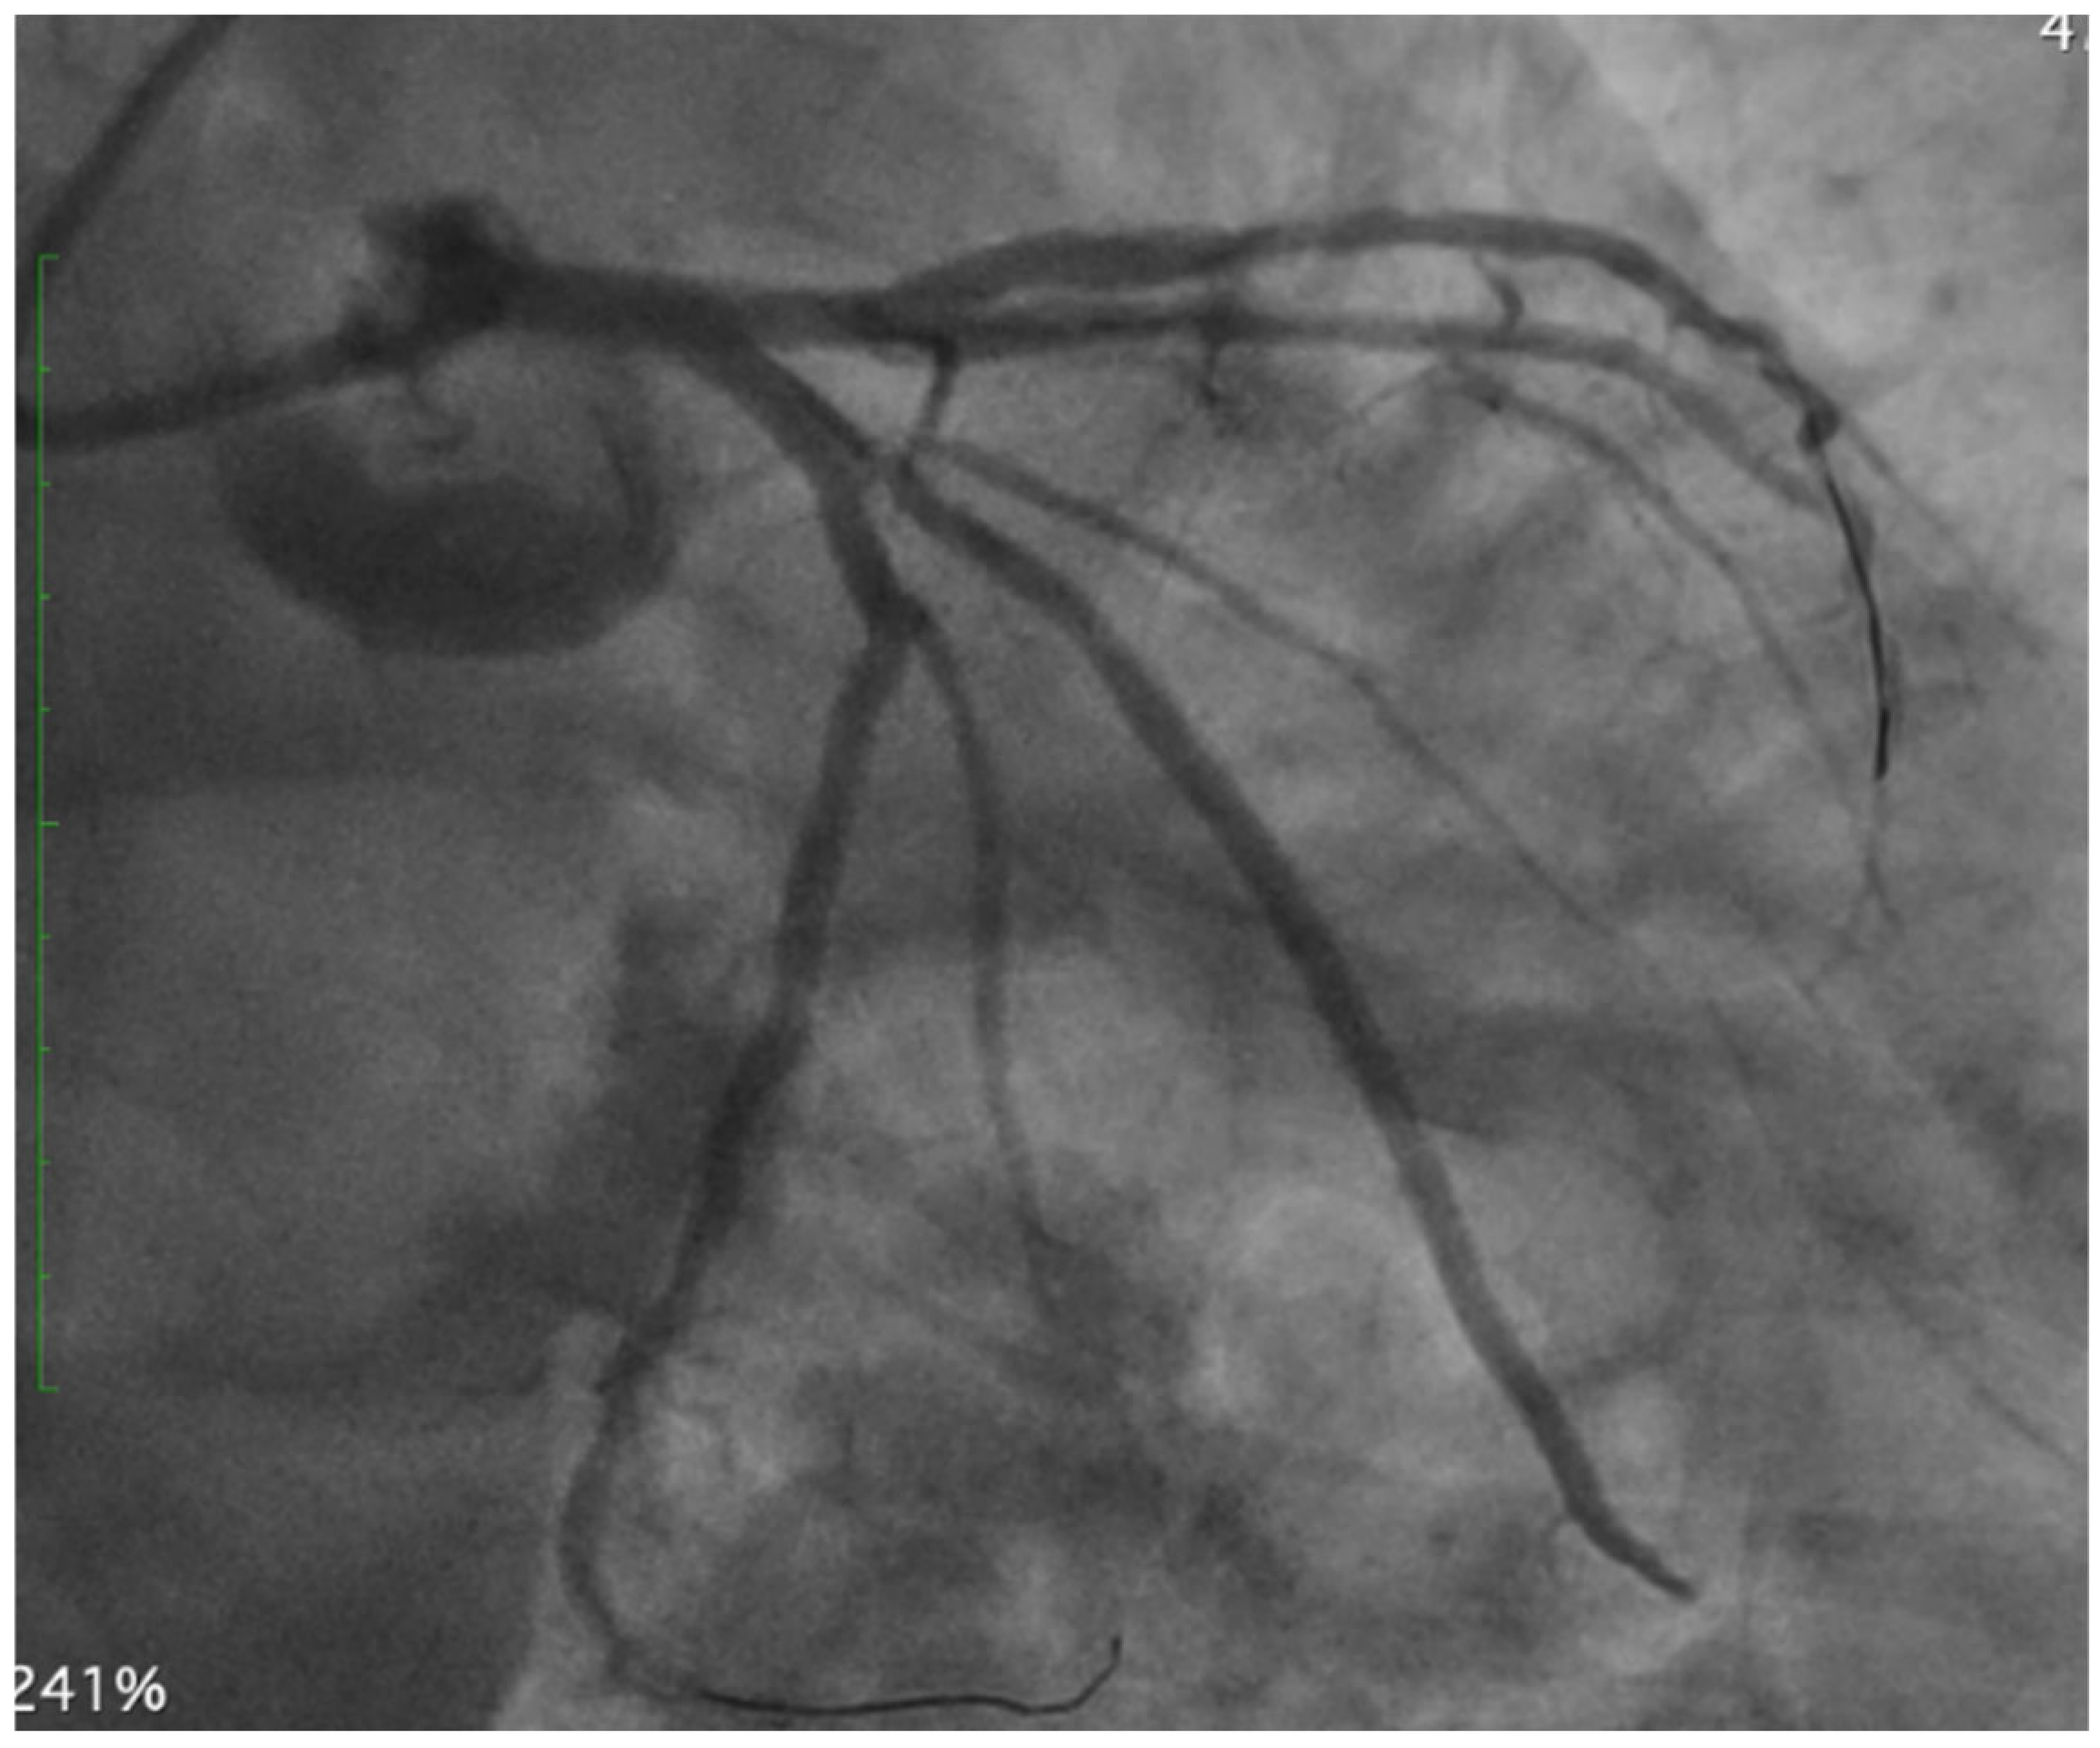

As shown in Figure 5, the final angiographic result demonstrates the successful treatment of the bifurcation lesion using a two-stent strategy (TAP technique), with optimal stent expansion, complete restoration of luminal patency, and final TIMI 3 flow in both the LAD and LCx.

Figure 5.

Final angiographic result. Angiography shows optimal lumen restoration following T-and-protrusion (TAP) stenting of the left main (LM) bifurcation involving the left anterior descending (LAD) and left circumflex (LCx). Abbreviations: PCI, percutaneous coronary intervention; LM, left main; LAD, left anterior descending; LCx, left circumflex; TAP, T-and-protrusion.